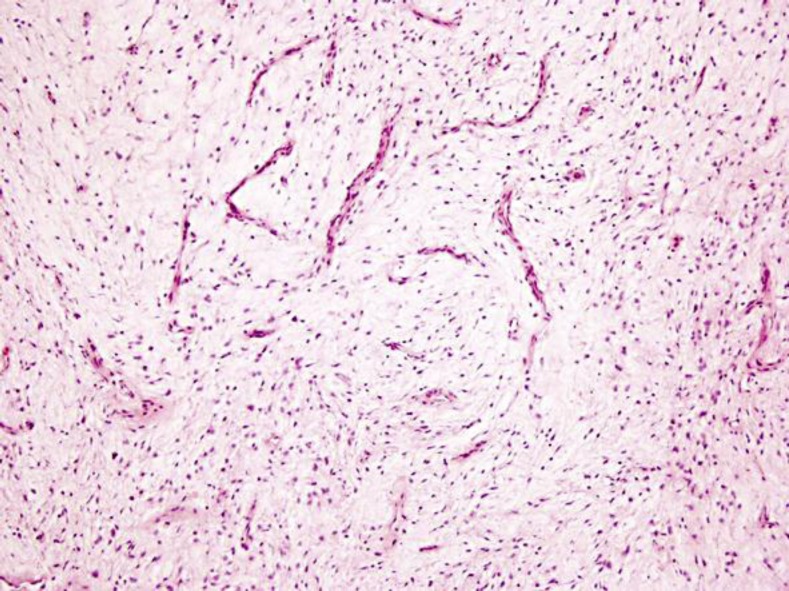

发生在泌尿生殖系统的肉瘤十分罕见,约占所有软组织肉瘤的2.1%,预后较差。肾肉瘤相当罕见,约占恶性肾病例的1-3%。肾脏低级别纤维黏液样肉瘤(LGFS)是一种非常罕见的,惰性但转移的软组织肉瘤,具有看似良性的组织学特征。估计5年总生存率超过90%,但可能发生很晚的局部复发和远处转移,这强调了长期随访的必要性。我们报告一例48岁男性患者的LGFS位于肾盂。这可能是第一次报道起源于肾盂的LGFS。

Sarcomas of the genitourinary tract are quite rare, accounting for 2.1% of all soft tissue sarcomas and have a poor prognosis. Kidney sarcomas are quite rare, representing 1–3% of malignant renal cases. Low-grade fibromyxoid sarcoma (LGFS) of the kidney is an exceedingly uncommon, indolent but metastasizing soft tissue sarcoma with deceptively benign-appearing histological features. The estimated 5-year overall survival seems to be over 90%, but very late local relapses and distant metastasis may occur, which underlines the need for a long-term follow-up. We present a case of a 48-year-old male patient with a LGFS located on the renal pelvis. This is probably the first report of LGFS arising from the renal pelvis.